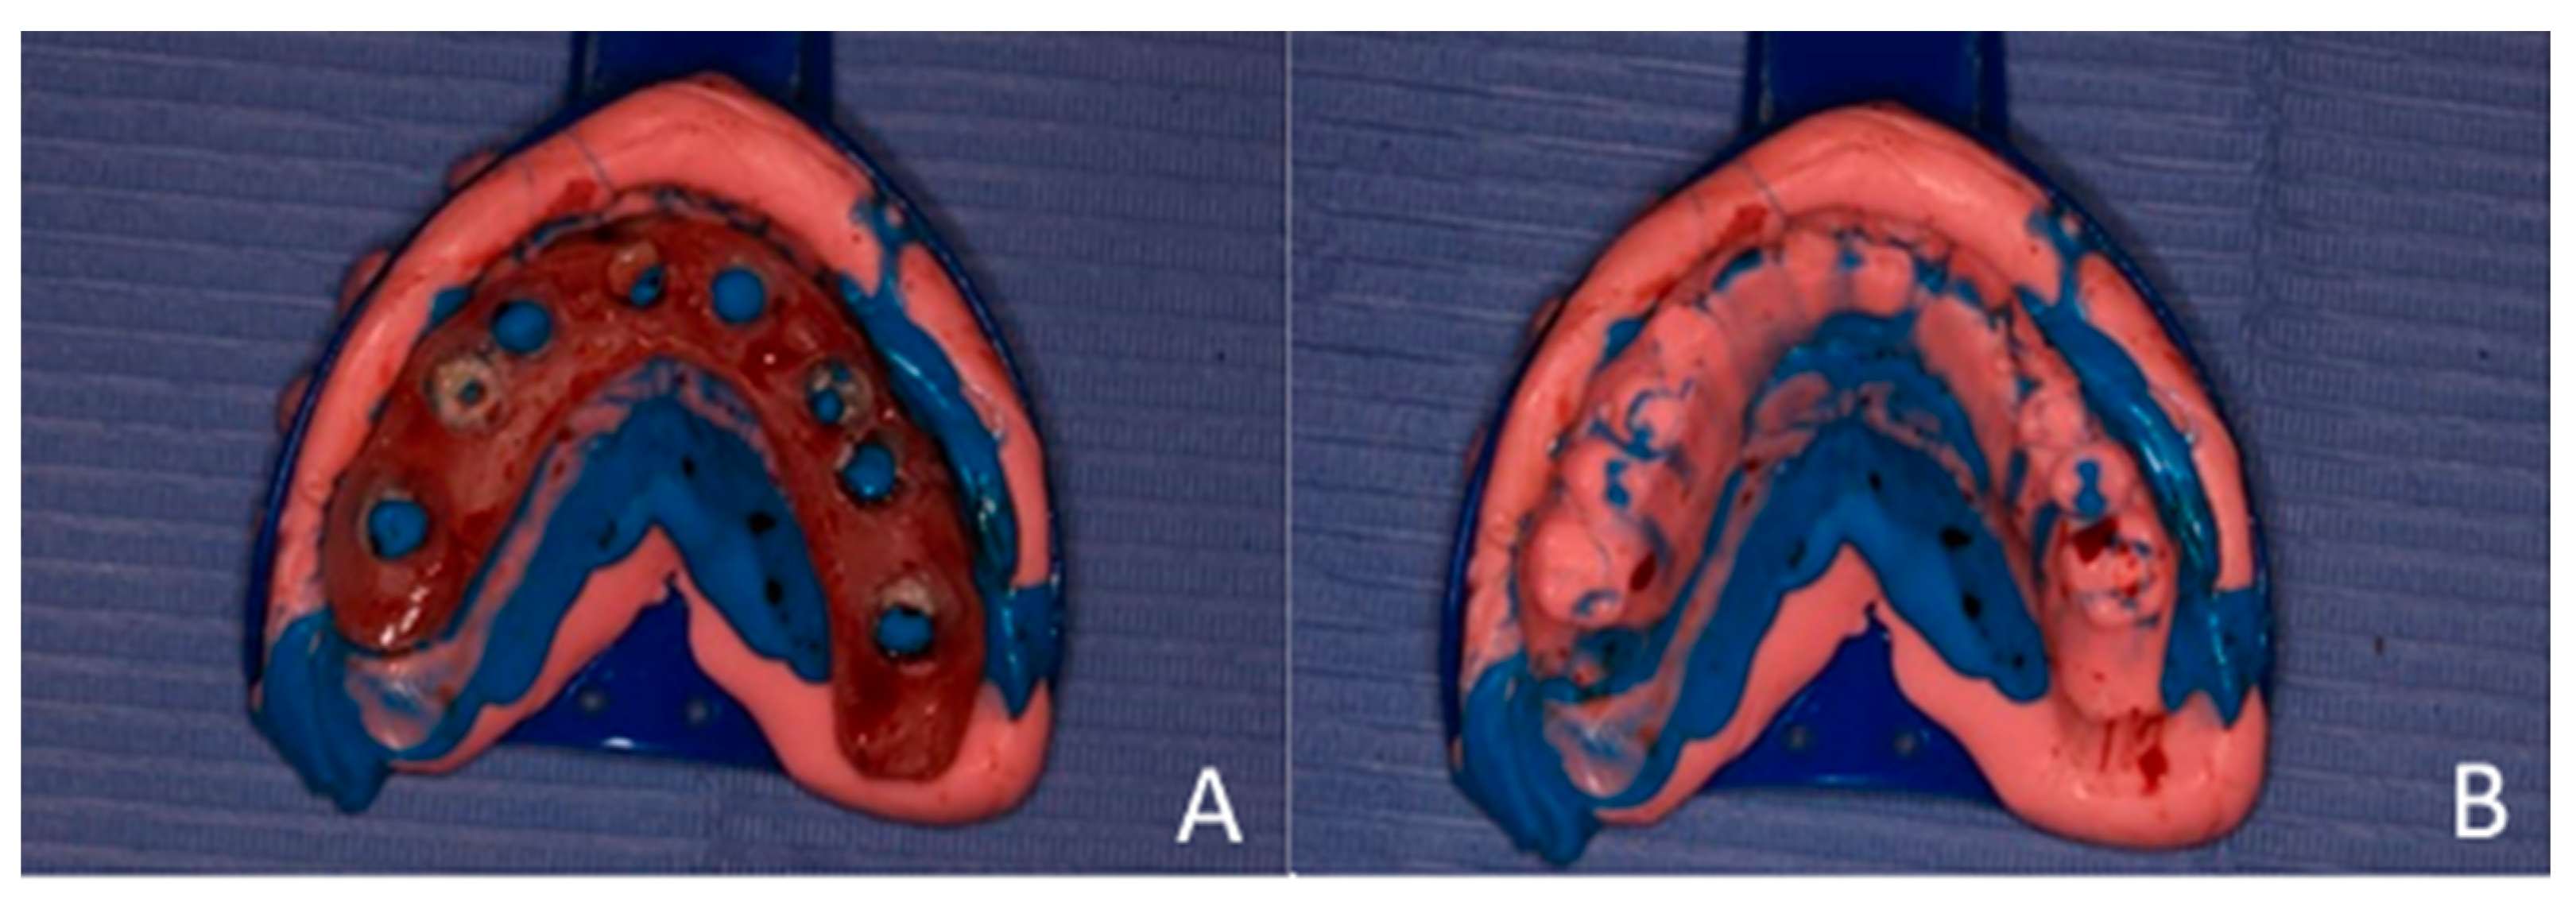

An impression was made using additional silicone, combined with soft and hard putty, for a one-step pickup impression. After the impression material set, the dentures were removed and used as a key or index to fabricate chairside temporary bridges (Figure 8).

Figure 8. (A) Fabrication of temporary bridges. The modified upper denture was picked with the additional silicone impression material. (B) Index for the temporary bridge.